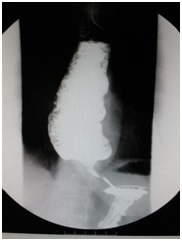

术前(食管中下段管腔明显扩张,贲门呈鸟嘴样狭窄) POEM术后(贲门开放良好)